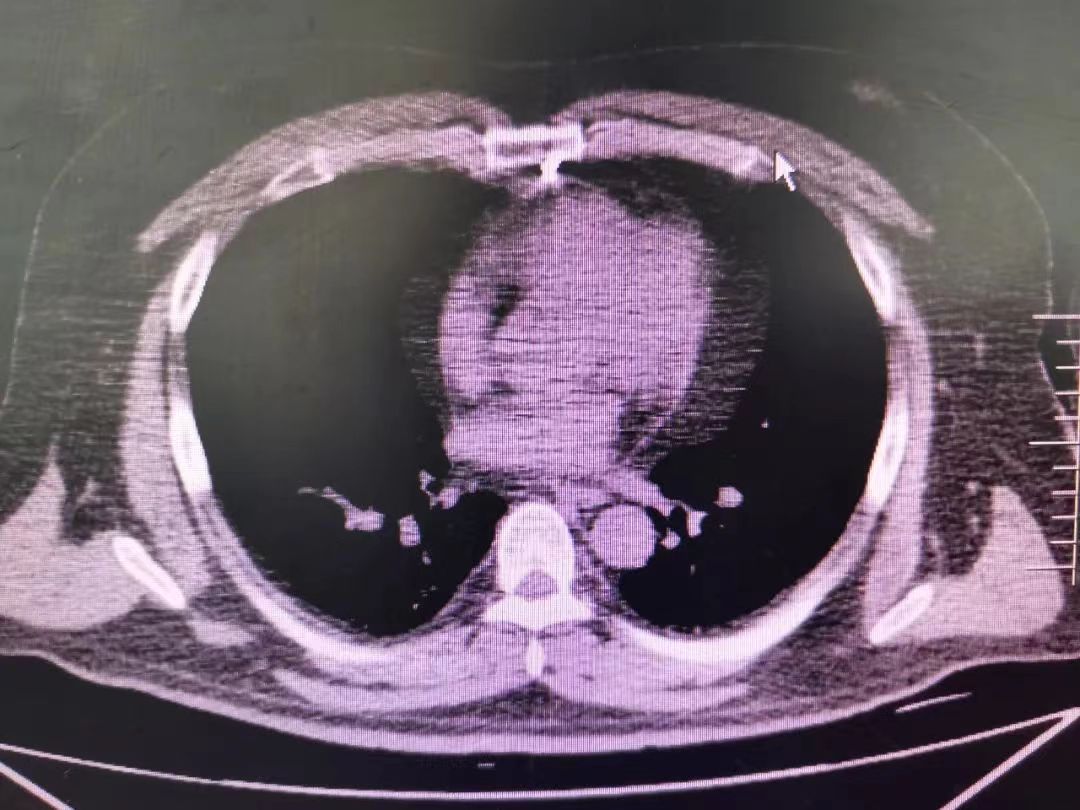

CT室門口,焦燥的家屬不停的走動(dòng)著、等待著,看到醫(yī)生的到來,快速跑到醫(yī)生面前說:“醫(yī)生,快幫我看看,病人怎么樣”。陳醫(yī)生過去一看,一個(gè)體型偏胖的患者平躺在床上,一把剪刀齊根直插胸口觸目驚心,陳醫(yī)生不由眉頭一緊,轉(zhuǎn)身去看電腦CT影像 --剪刀斜著刺入胸骨,將胸骨完全穿透,刀尖距離心包約1-2mm,正下方是主動(dòng)脈,大量心包積液?再一看,患者肥胖,脂肪組織多,不排除脂肪偽影。考慮患者血壓相對平穩(wěn),由于緊張導(dǎo)致心率快,立刻安撫患者,讓其保持安靜,盡量避免咳嗽,避免深呼吸和過多運(yùn)動(dòng)。隨即撥通了武小剛主任的電話:“主任,這有一位患者,銳器刺傷不排除已經(jīng)損傷到心臟,病人目前血壓平穩(wěn)”“嚴(yán)密監(jiān)測患者病情變化,準(zhǔn)備急診手術(shù),我馬上到”武主任說。